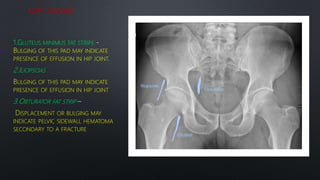

SOFT TISSUES

1.GLUTEUS MINIMUS FAT STRIPE

BULGING OF THIS PAD MAY INDICATE

PRESENCE OF EFFUSION IN HIP JOINT

2.ILIOPSOAS

3.OBTURATOR FAT STRIP

DISPLACEMENT OR BULGING MAY

INDICATE PELVIC SIDEWALL HEMATOMA

SECONDARY TO A FRACTURE